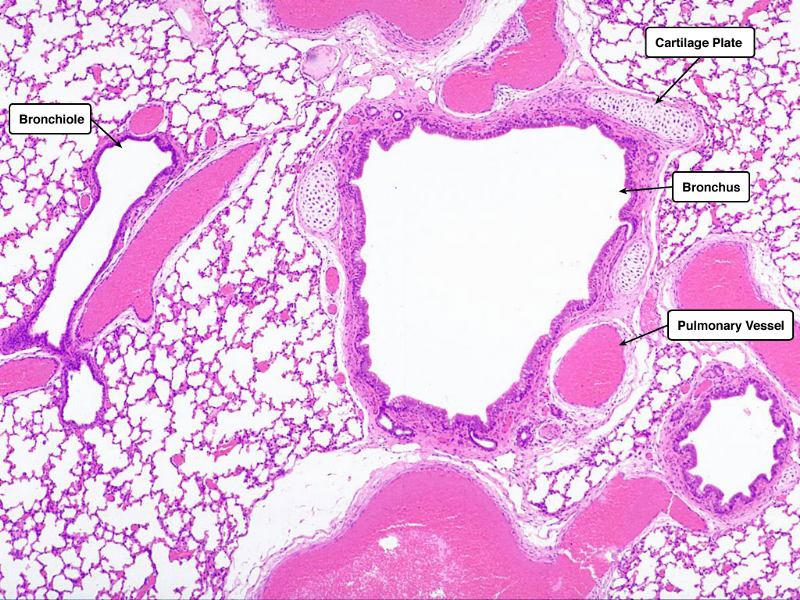

Go with the flow

Trace the air flow of respiratory system starting with the nostrils.

What path does a molecule of oxygen take to reach the blood?

What sights will it see along the way?

1. Outside air

2. ??

3. ...

4. Toes

Path of O2

• List complete

• With layers

• And cells

• And function of each

• By studying and labelling images